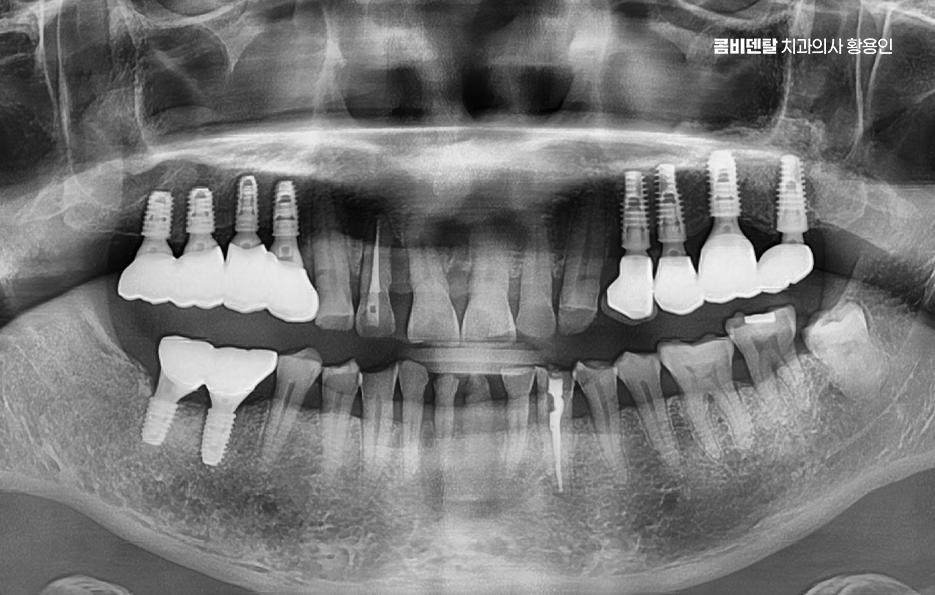

어금니 임플란트 과정은 정밀 진단에서 시작되며 잇몸뼈 안에 인공 치근을 심는 방식이기 때문에 뼈 상태 확인이 필수적으로 파노라마 촬영이나 3차원 CT를 통해 뼈 높이와 폭, 신경 위치를 확인하고 특히 아래 어금니는 하치조신경과 가까워서 정확한 위치 파악이 중요하며 위 어금니는 상악동과의 거리도 고려해야 할 필요가 있어요

임플란트를 심을 잇몸 뼈가 충분하다면 바로 식립이 가능하지만 치아를 빼고 오래 방치한 경우에는 뼈가 흡수되어 부족할 수 있으며 이때는 뼈이식을 먼저 하거나 동시에 진행하고 어금니는 씹는 힘이 강하기 때문에 초기 고정이 단단해야 하며 유지까지 고려할 때 교합의 정교한 맞물림이 중요한 부위라고 할 수 있었어요

어금니 임플란트 과정에서 수술 당일에는 국소마취 후 잇몸을 절개하거나 최소 절개로 접근해 뼈에 임플란트를 식립하며 수술 후에는 일정 기간 골유착을 기다리는데 임플란트와 뼈가 단단히 결합하는 과정이라 할 수 있었어요

골유착이 완료되면 지대주를 연결하고 본을 떠서 최종 보철물을 제작하며 어금니 크라운은 강도와 교합 조화를 동시에 고려해 제작하는데 씹는 힘이 집중되는 부위이기 때문에 높이와 접촉점 조정이 중요하며 교합이 맞지 않으면 나사가 풀리거나 보철물에 문제가 생길 수 있어서 장착 후에도 교합 점검 및 정기적인 검진, 스케일링 등의 관리가 중요할 수 있어요

흔히 임플란트는 충치가 생기지 않는다고 생각하는 경우가 많은데 잇몸 염증은 충분히 생길 수 있으며 임플란트 주위염이 발생하면 뼈가 녹아 실패로 이어질 수 있어서 치간칫솔이나 치실을 사용해 꼼꼼히 관리하고, 정기 검진을 통해 뼈 상태를 확인해야 하고 특히 어금니는 음식물이 잘 끼는 위치라 더 신경 써야 한다는 점에서도 치료 계획 만이 아니라 유지 관리까지 포함한 장기적인 케어가 중요하다고 볼 수 있었어요